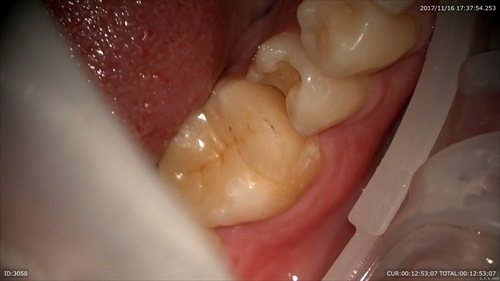

セラミックの詰め物ケース

前回神経を保護する治療を行い。

「最初はしみていたけど、今は良くなった」と喜んでいました。

研磨

セット。おいしい物沢山食べてください!!